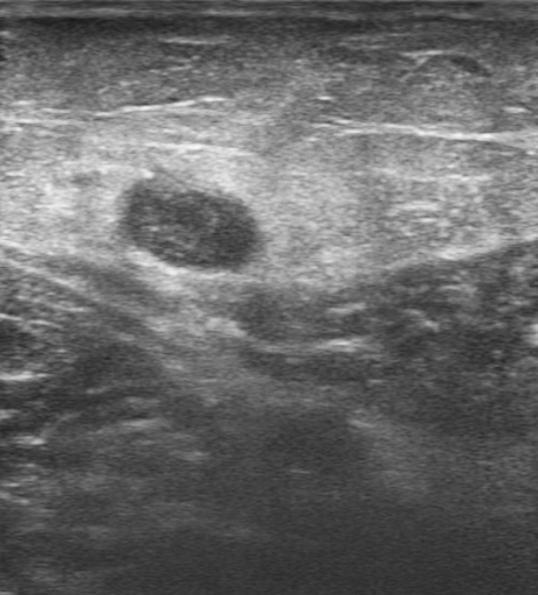

Ecografía de miembro inferior izquierdo: contenido hiperecogénico en todo el trayecto de la vena safena interna, no compresible. Sistema venoso profundo permeable sin datos de TVP (Imagen 2,3,4).

Tromboflebitis en todo el territorio de vena safena interna de miembro inferior izquierdo.

Tras descartar TVP, ausencia de signos clínicos, analíticos y ecográficos de alarma, se decide manejo ambulatorio con vendaje compresivo, antiinflamatorios vía oral e inicio de Enoxaparina 100 mg cada 12 h (dosis terapéuticas) durante 45 días.